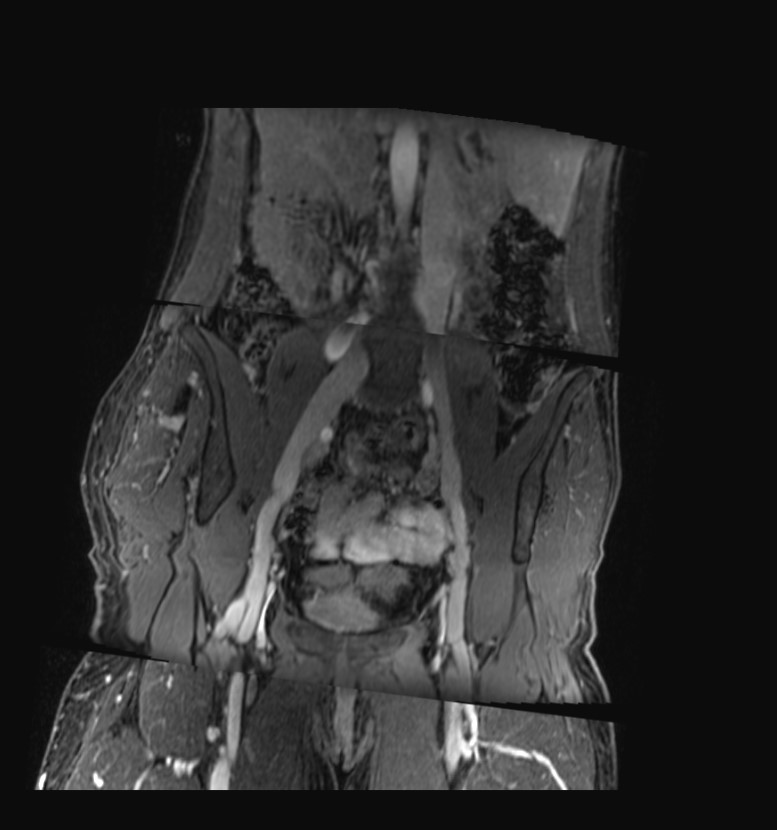

In addition to CT venography, our service incorporates MR venography, which is specifically valuable for displaying the venous system in the abdomen, pelvis, and lower extremities. This modality is particularly adept at assessing various venous conditions, including stenosis, the presence and condition of stenting, post-thrombotic changes, varicose alterations, and evaluating the saphenous vein for bypass suitability.